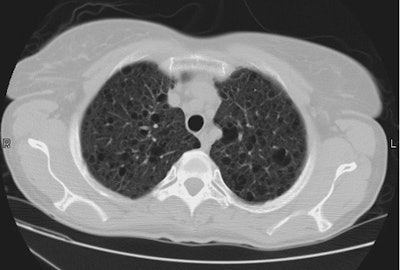

Diaphragmatic Rupture:

The patient shown below presented following a motor vehicle accident. The CXR demonstrated abnormal opacification over the lower left hemithorax which was very suggestive of a diaphragmatic injury.

CT imaging confirmed the presence of a diaphragmatic tear. The diaphragm was discontinuous, the stomach and bowel loops can be identified in the thoracic cavity, and there was also a dependent visera sign.